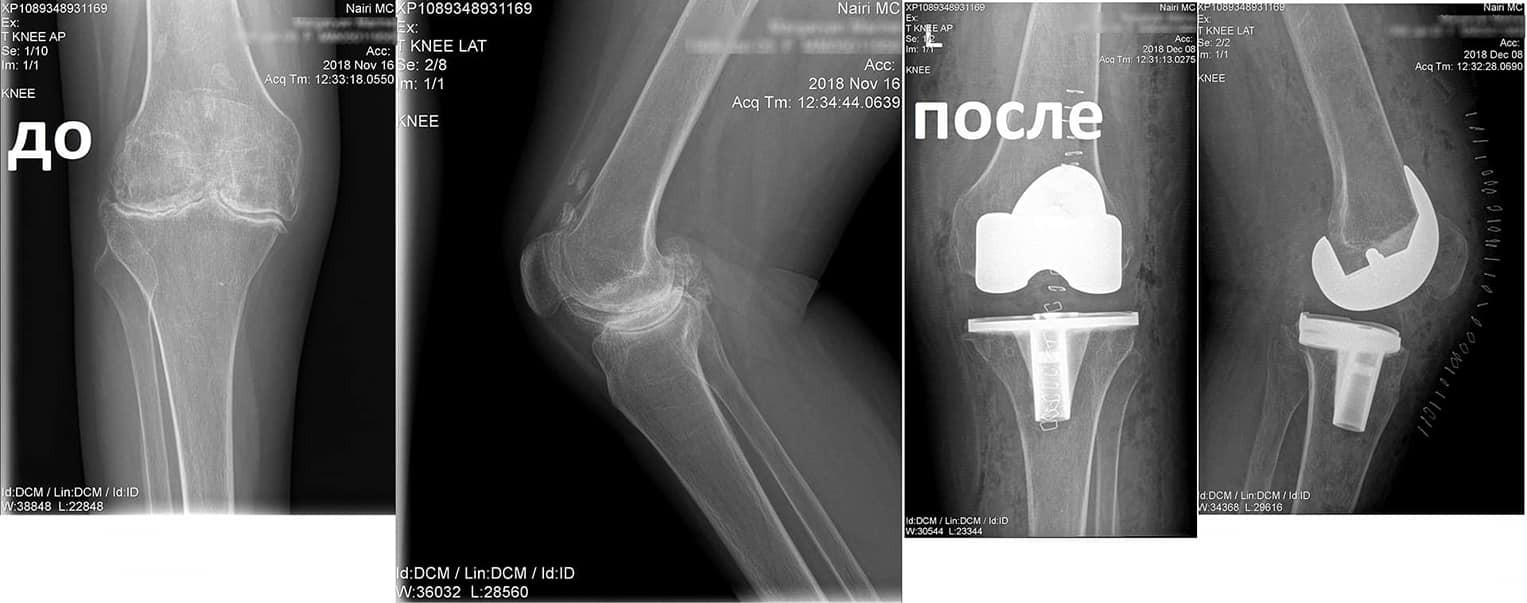

Կլինիկական դեպք. երկկողմանի գոնարթրոզ՝ ծնկահոդերի արթրոզ

Պացիենտը դիմել էր «Նաիրի» բժշկական կենտրոն` նստասալյակի օգնությամբ, ծանրագույն ցավերով, շարժումների խիստ սահմանափակումով:

Ծանրագույն պոլիարթրիտի հետևանքով առաջացել էր ծնկահոդերի արթրոզ։

Ըստ անամնեստիկ տվյալների, երկար ժամանակ կիրառում է մեծ չափաբաժիններով ստերոիդ դեղեր:

Նման դեպքերում վիրահատույթունից առաջ պահանջվում է լրջագույն նախապատրաստում և հետվիրահատական հսկողություն:

Նախավիրահատական ընթացակարգից հետո իրականացվել է զույգ ծնկահոդերի փուլային էնդոպրոթեզավորում: Վիրահատությունից մի քանի ամիս անց պացիենտը չի ունեցել ցավեր, ազատ քայլել է և սկսել է ապրել լիարժեք կյանքով: